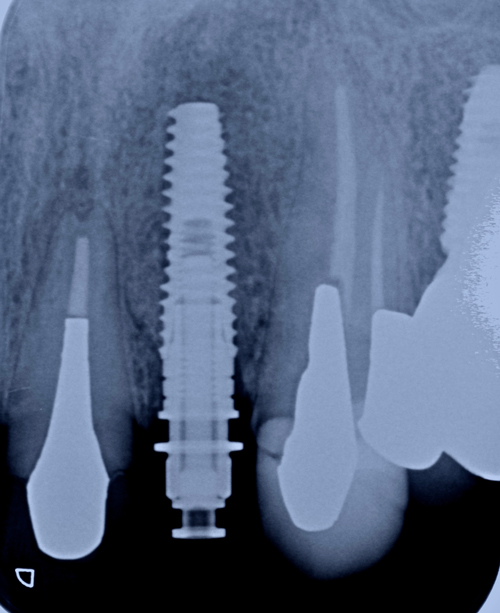

CT画像の診断結果、歯根破折による大きく骨の欠損及び腫瘍の発生。即抜歯を必要とする診断。

唇側の半分がほとんど骨が失われていました。この状態からインプラントを移植して、不足している骨も同時に再生定着

させていきます。